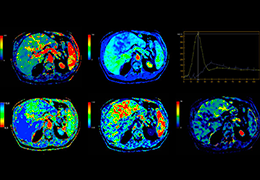

High-quality and fast 3D reconstruction and 3D rendering

Performs 3D reconstruction and volume rendering.

Side-by-side comparative assessment for pre- and post-operative scans.